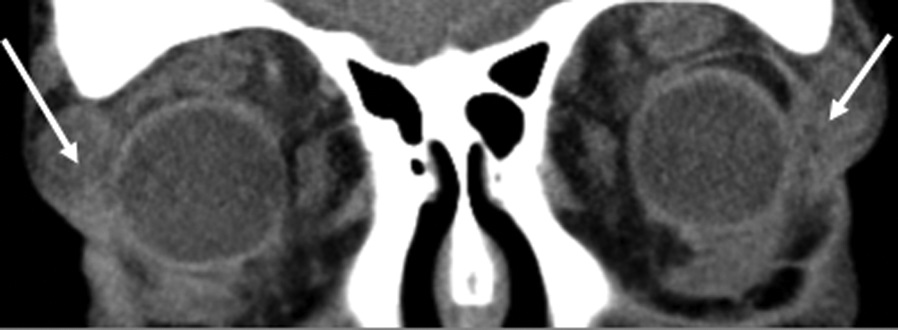

Рис. 8. Клинические проявления эндокринной офтальмопатии с оптической нейропатией. б — МСКТ орбит, корональная проекция — сдавление зрительного нерва (белые стрелки) у вершины орбиты увеличенными в объеме ЭОМ.

Увеличение объема ЭОМ в области их брюшка и в зоне Циннова кольца у вершины орбиты приводит к компрессии ЗН, нарушению кровотока и повышению внутриглазного давления. К томографическим признакам ОН относится и синдром «апикального сгущения» (рис. 8 на цв. вклейке, см. раздел Дополнительная информация). Этот синдром при ОН выявлялся значимо чаще, чем натяжение ЗН: соответственно в 62 и в 47% случаев. Синдром «апикального сгущения» определяется как исчезновение периневральной жировой ткани в задней части глазницы. Сочетание апикального сгущения с признаками выпячивания жировой ткани через верхнюю глазничную щель считается надежным диагностическим критерием ОН, специфичность которого достигает 91%, а чувствительность — 94%. При компьютерной периметрии выявляются центральные и парацентральные скотомы с последующим выпадением полей зрения.

Рис. 9. Выраженный двусторонний лагофтальм. б — компрессия зрительного нерва (белые стрелки) у пациентки с тяжелой формой ЭОП, осложнившейся оптической нейропатией и выраженным экзофтальмом.